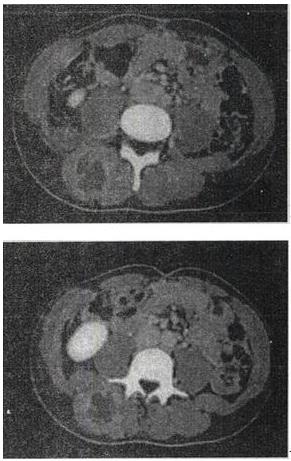

- 单项选择题 女,28岁,右肾区疼痛伴高热,根据所示图像,最有可能的诊断是()。

- E